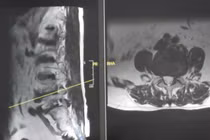

Hình ảnh thoát vị đĩa đệm cột sống cổ - Ảnh minh họa/Nguồn SKĐS